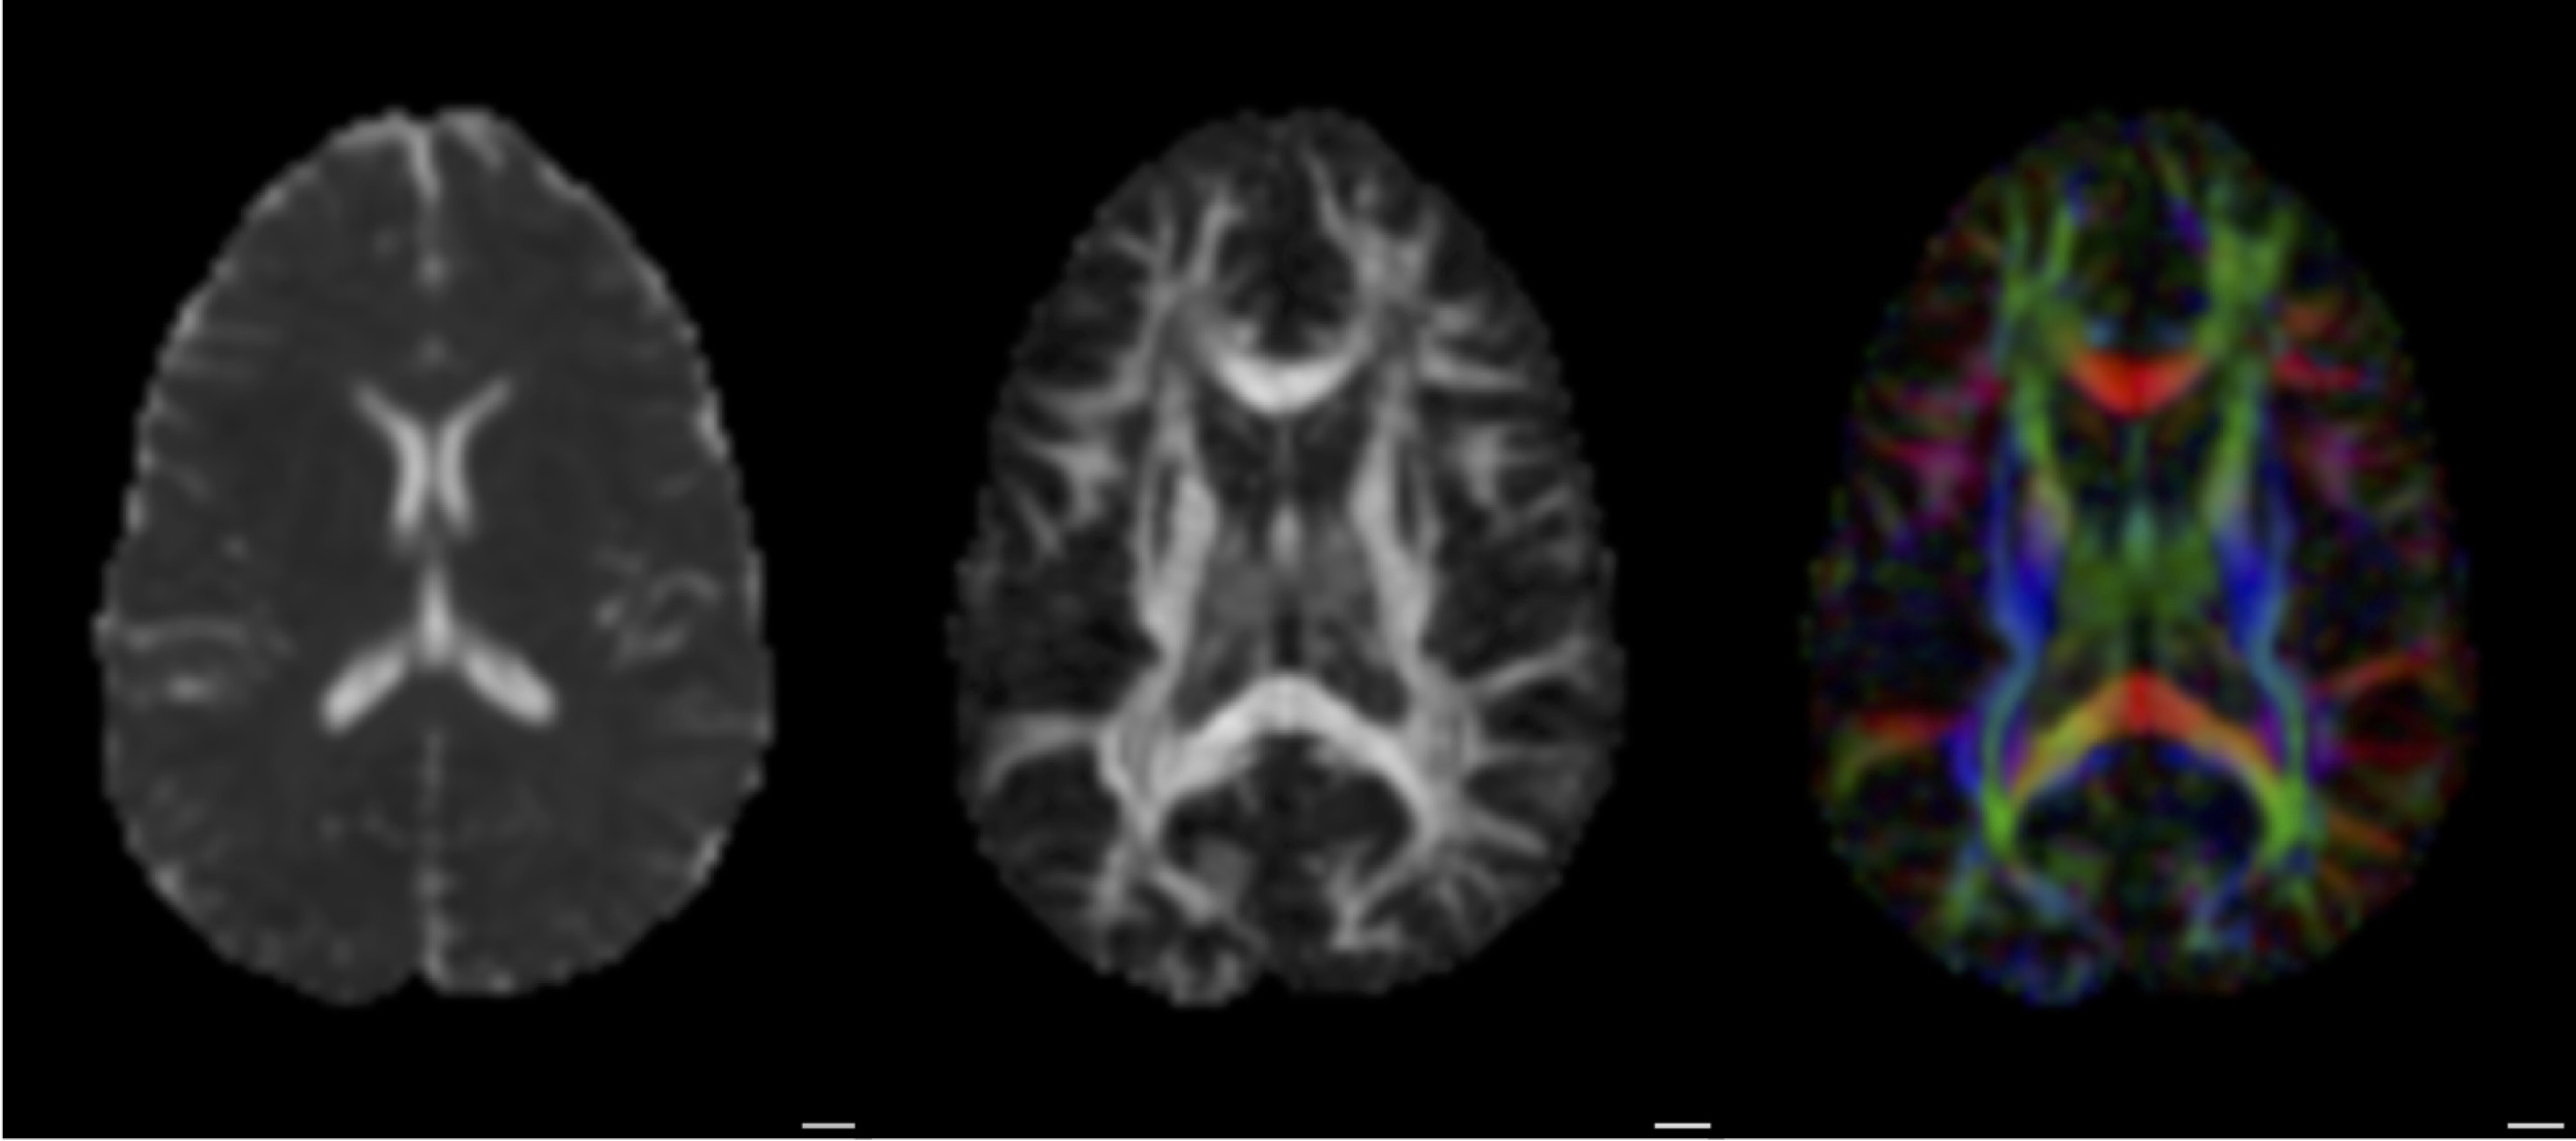

Basser (1994), Basser and Pierpaoli (1996)